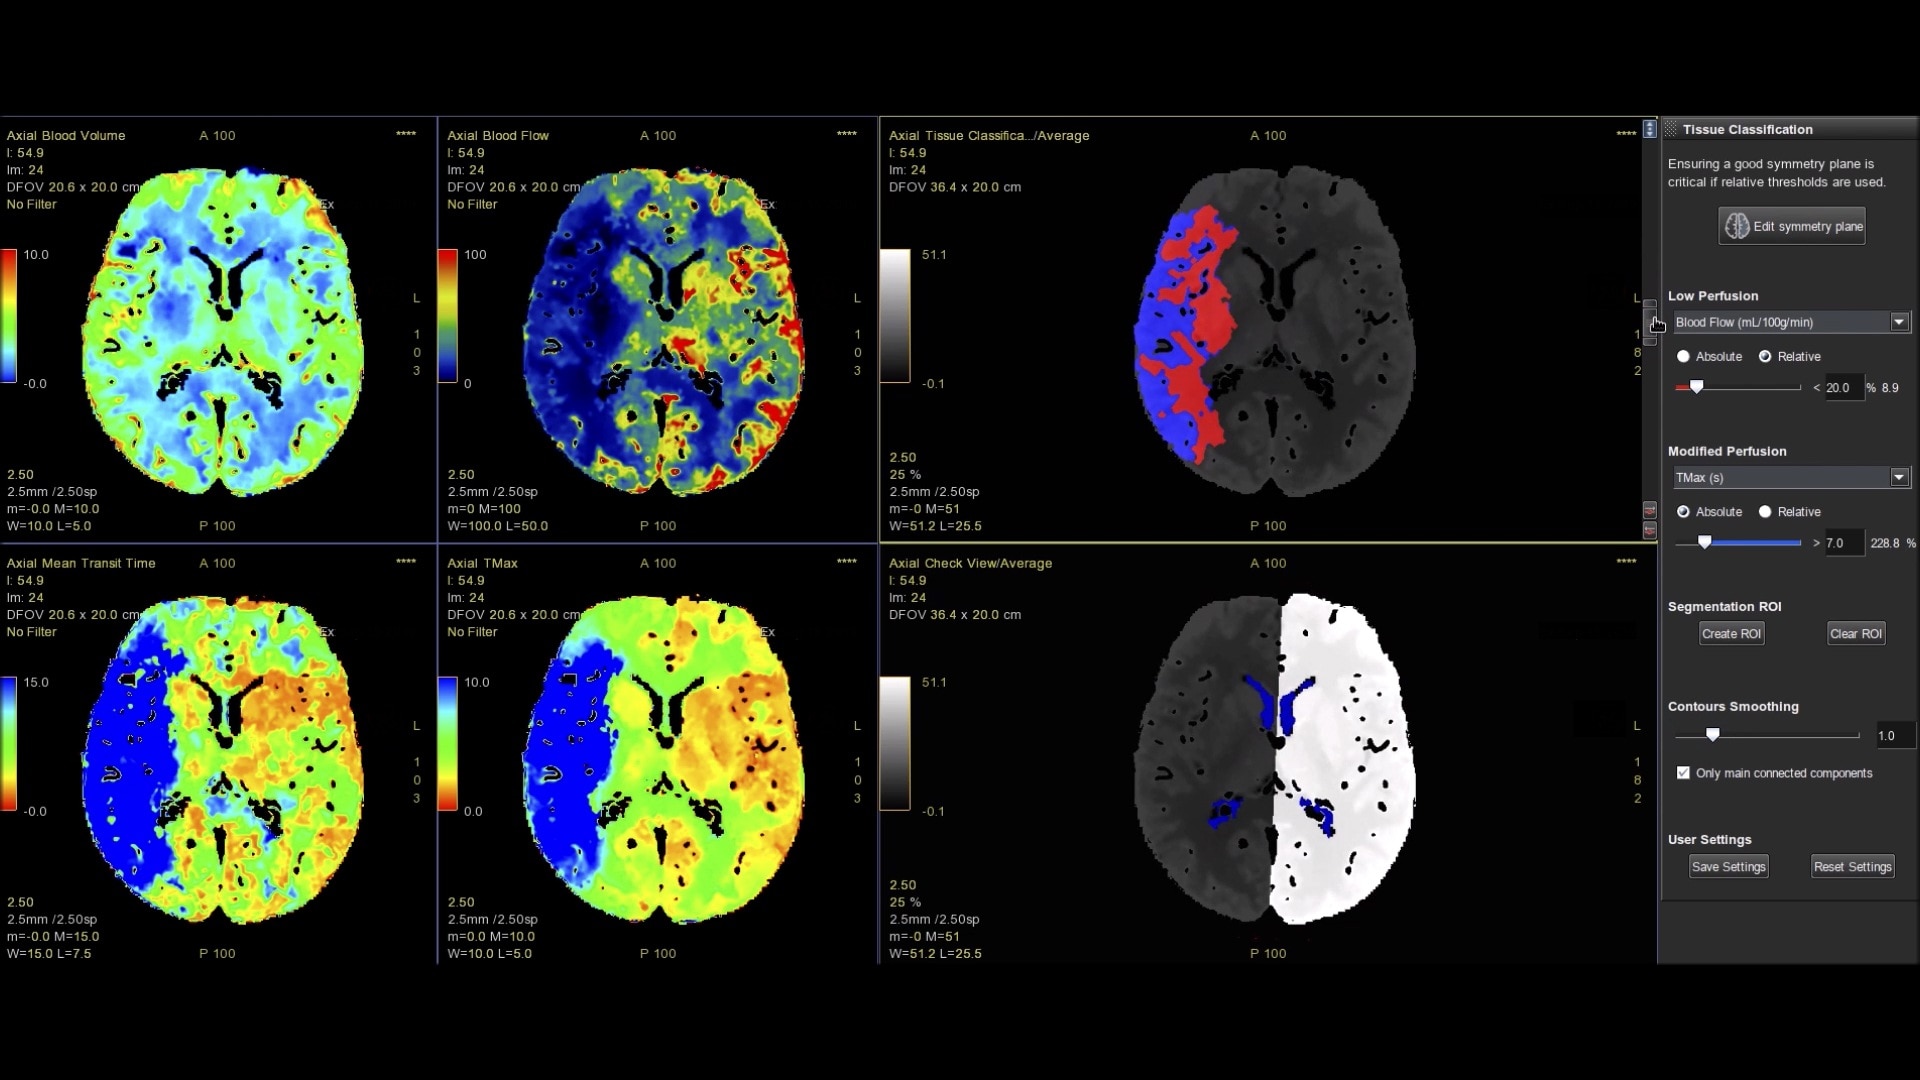

Perfusion maps and tissue classification

• Fully integrated with CT Perfusion 4D for visualization of perfusion functional maps³

• Deep Learning brain ventricle segmentation to prevent ventricular matter inclusion in quantitative results and improve visual inspection of the maps

• Automated computation of the functional maps

• Tissue Classification map segmented from absolute or relative values, customizable thresholds and user selectable input maps

• Mismatch volume and ratio calculated from the Modified Perfusion region and the Low Perfusion region